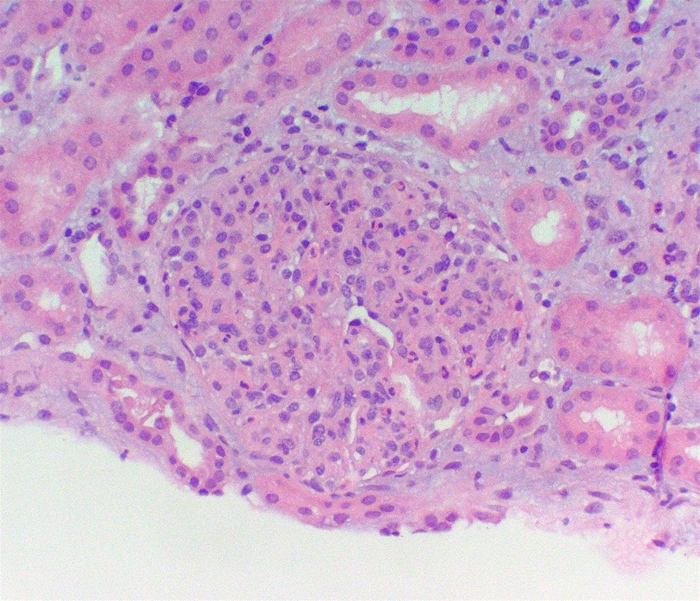

A 12-year-old boy is brought to the clinic because of facial puffiness.  Examination shows periorbital edema.  Urinalysis reveals: A 12-year-old boy is brought to the clinic because of facial puffiness.  Examination shows periorbital edema.  Urinalysis reveals:   A biopsy image representative of this patient's disease process is shown below.   Which of the following additional findings is most likely to be present in this patient? A) Antiglomerular basement membrane antibodies B) Antineutrophil cytoplasmic antibodies C) Decreased serum C3 level D) Decreased serum C4 level E) Increased eosinophil count A biopsy image representative of this patient's disease process is shown below. A 12-year-old boy is brought to the clinic because of facial puffiness.  Examination shows periorbital edema.  Urinalysis reveals:   A biopsy image representative of this patient's disease process is shown below.   Which of the following additional findings is most likely to be present in this patient? A) Antiglomerular basement membrane antibodies B) Antineutrophil cytoplasmic antibodies C) Decreased serum C3 level D) Decreased serum C4 level E) Increased eosinophil count Which of the following additional findings is most likely to be present in this patient?